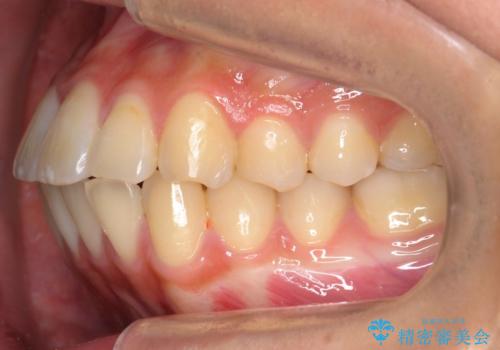

20代女性 八重歯 奥歯の反対咬合 前歯のがたがた 急速拡大装置で

- 八重歯を主訴に来院。

上顎の幅が狭く、左側の臼歯が反対咬合でした。

20歳前後で若かったため、急速拡大装置で上顎骨を横に広げてから矯正を行いました。

急速拡大装置で3ヶ月保定した後、マルチブラケット装置で並べました。

上下の小臼歯を抜歯しています。

歯だけ頬側に倒す形で歯列を拡大してしまうと、外側に倒れてしまい、機能咬頭同士できちんとかむことができません。

本症例では、上顎の狭窄歯列を予め急速拡大装置で土台ごと広げることにより、奥歯の適切なオーバーバイトを獲得することができました。

また、八重歯だった犬歯もきちんと歯列に収めています。